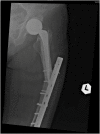

We report an 85-year-old patient with severe osteoporosis who had suffered from multiple episodes of periprosthetic fracture of the femur. Revision fixation with long-spanning cable plate for bisphosphonate-induced atypical periprosthetic femoral fracture was performed. Nonunion and implant failure occurred at 16 months requiring revision surgery using long-stem femoral prosthesis with cable-plate fixation. To further facilitate bone healing, allograft and bone morphogenetic protein (BMP) were added. Eventually bone union was achieved after one year.